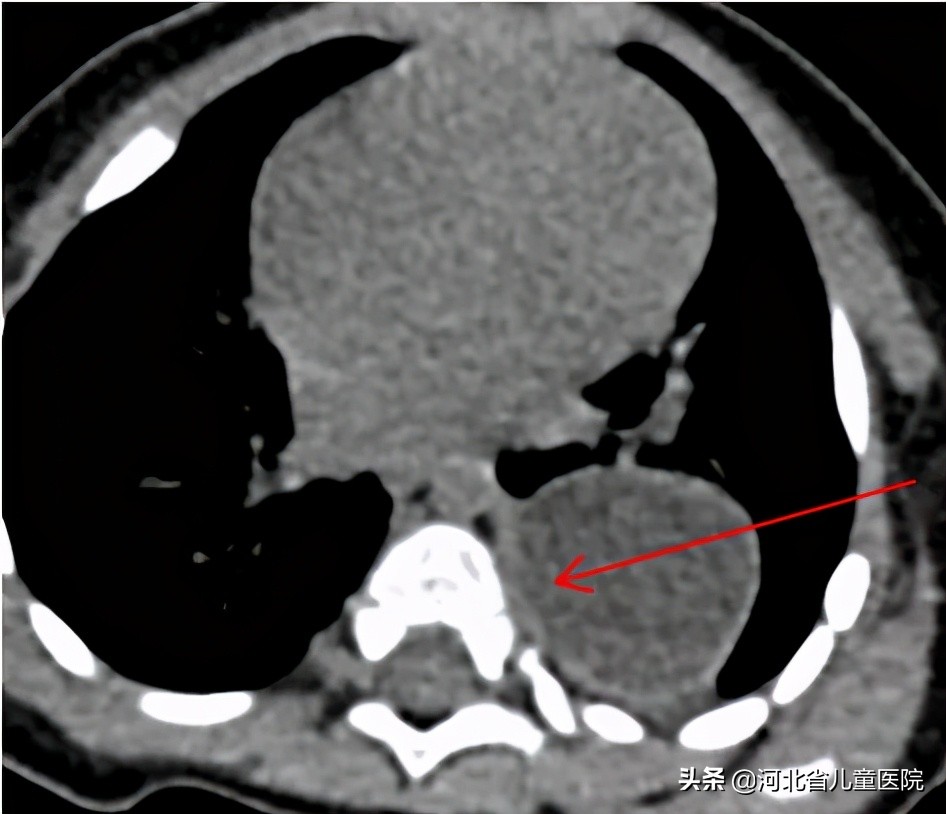

9个月的乐乐,因为咳嗽检查胸部CT,发现存在巨大的纵隔占位,乐乐爸妈很是费解,孩子平时也没啥症状,怎么会纵隔长个东西呢?

为什么乐乐的纵隔肿瘤长得很大,却没啥症状呢?原来,纵隔肿瘤 临床表现变化很大:

所幸,乐乐的纵隔占位经手术切除,术后恢复顺利,病理回报是良性的囊肿,大家悬着的心也终于能放下了。